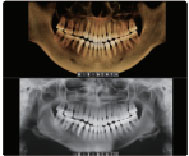

Autotransversal[3D PAN] Tab

Tab-ul [3D PAN] din Ez3D-i face totul rapid şi inteligent.

Acest mod volumetric – panoramă facilitează diagnosticul în regiunea linguală. De asemenea, localizarea unei leziuni în timpul unui tratament endodontic este eficientă şi precisă, chiar dacă este aproape de zona apicală.